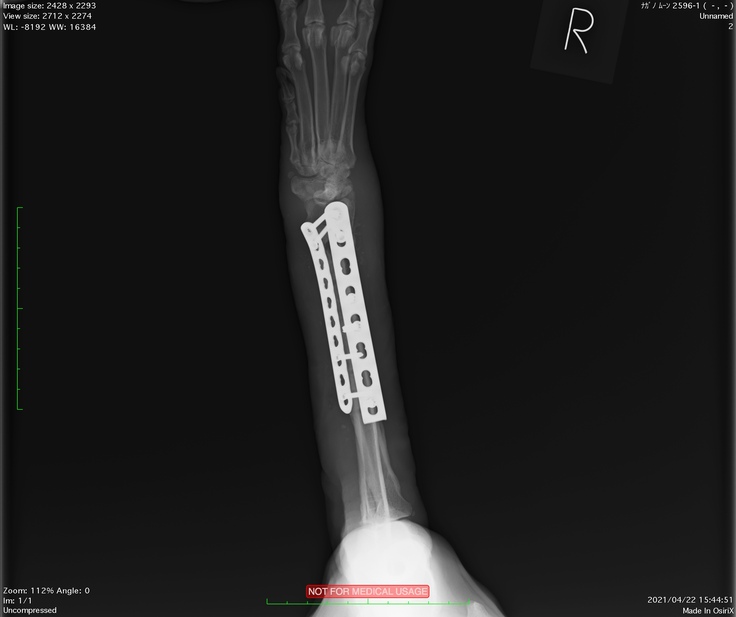

大津動物クリニックではクラウドファンディングのお話をしたらレントゲンの画像もご提供いただけました。

2度目の手術後のレントゲンです。まっすぐになりました。

右前足の開放骨折 2度のプレート固定手術